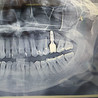

Требовалась установка двух имплантов "под ключ". Выбирал между тремя клиниками, в данную стоматологию обратился по рекомендации знакомого уже в последний момент. Осмотр занял 15 минут. Понравилось, что при первичном осмотре мне на мониторе показали все мои зубы и объективные недостатки по ним. Услуги не навязывали, предложили только чистку, которую я давно и собирался делать. Координатор Александра работу свою выполняет хорошо, быстро все посчитала, обозначила сроки и договоренности все были исполнены точно и в срок. Стоимость услуг и материалов нормальная. Мастера опытные, оперировал хирург Силаев, коронки ставила ортодонт Быкова. В декабре 2024 года импланты установили, срок эксплуатации три месяца, полет нормальный )) буду обращаться дальше, рекомендую.

Однажды треснул зуб! Посетил клинику Все Свои по адресу Маршала Малиновского 6 к 1. Я посетил доктора Магомеда Арсейновича, он направил меня на снимок. Далее сказал что зуб треснут под корень и его нужно удалять. Потом мне менеджер рассказал все по ценам и акциям. Очень переживал что удаление зуба будет болезненно но оказалось что совсем не больно. Анестезия хорошая... Буквально 10 минут и все готово, а самое главное что без боли. Очень благодарен хирургу Магомеду Арсейновичу за его работу! Буду советовать друзьям! Еще раз спасибо!